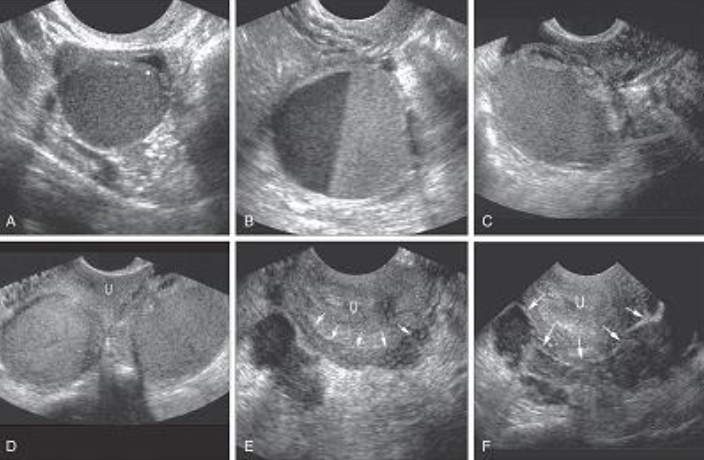

Benign disease

Diffuse or focal

Global infiltration of endometrium

Sonographically presents as bulky enlarged uterus without focal mass

Adenomyosis is ectopic occurrence of endometrial tissue within myometrium; more common in

posterior aspect

The tissue penetration usually reaches a depth of at least 2.5 mm from the basal layer of the

endometrium.

Adenomyosis may arise from multiple pregnancies and deliveries with subsequent uterine shrinking.

Elevated estrogen levels may also promote the growth of myometrial islands of endometrial tissue.

Adenomyosis is often classified into diffuse and focal forms. The more common form is diffuse

adenomyosis.

It represents a reactive hypertrophy of the myometrial muscle, which produces uterine enlargement

but usually not to the extent seen with leiomyomas.

Focal adenomyosis is sometimes called adenomyoma, referring to isolated implants that typically

cause reactive hypertrophy of the surrounding myometrium and produce diffuse uterine enlargement.

Less common than the diffuse form, focal adenomyosis (adenomyoma) lacks a hypoechoic border that

is seen with fibroids, not endometriosis. Adenomyosis can be appropriately managed with hormone

therapy.

Patients with adenomyosis are often multiparous and older than patients with endometriosis.

The patient presents with heavy, painful abnormal menses, and on physical examination, the uterus is

found to range from normal to three times normal size and is globular in contour, boggy, and

somewhat tender.

Sonographically, diagnosis may be difficult.

Most common presentation of extensive adenomyosis is:

➢ Diffuse uterine enlargement

➢ Thickening of posterior myometrium

➢ Indistinct border between endometrium and myometrium (involved area being slightly more

anechoic than normal myometrium)

Has been described as Swiss cheese or honeycomb pattern

Calcifications resulting from prior instrumentation are seen along inner myometrium and cervix.

Doppler studies have also proven helpful in differentiating uterine pathology, as color flow studies of

uterine masses show that myomas and sarcomas typically demonstrate a feeding artery, but

adenomyosis rarely demonstrates feeding arteries.

Adenomyosis is not always reliably diagnosed by ultrasonography, and

caution is advised because these findings are similar in appearance to

uterine myomas, muscular hypertrophy, myometrial contractions,

endometritis, endometrial carcinoma, and the presence of increased

endometrial secretions.

The presence of myomas has been shown to limit the ability to diagnose

the severity of adenomyosis.

Although not reliably diagnosed by ultrasonography, adenomyosis is well

characterized by MRI, which currently is thought by many to be the

best technique for the presurgical diagnosis of adenomyosis.

Adenomyosis